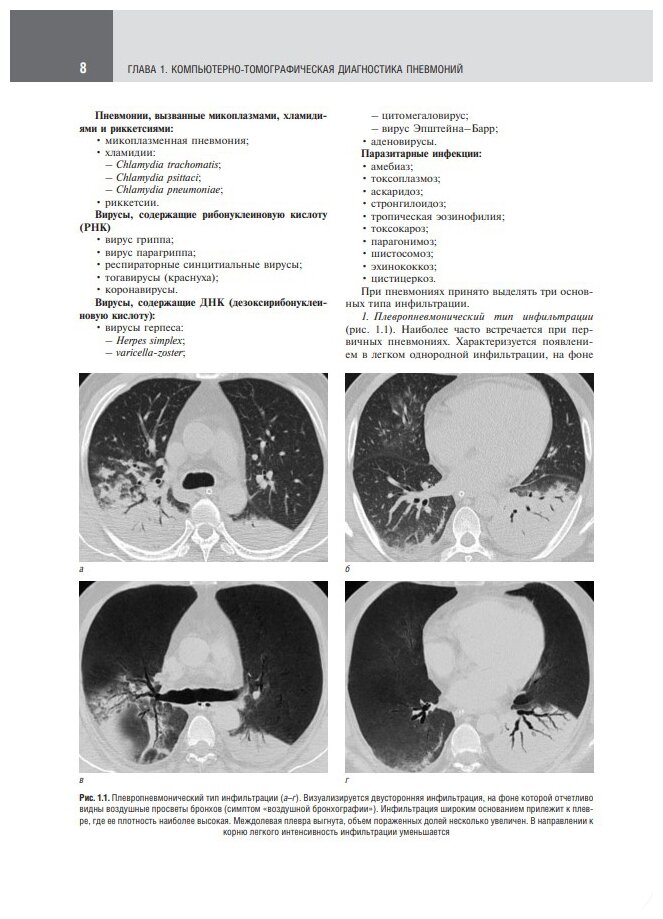

Атлас посвящен использованию рентгеновской компьютерной томографии в диагностике различных инфекционных заболеваний легких. В настоящее время общепризнана ведущая роль этого метода лучевой диагностики не только при первичном обследовании пациентов с подозрением на данные заболевания, но и в процессе лечения и динамического наблюдения в качестве метода контроля. Представлены изображения и комментарии к ним, которые могут использоваться врачами-рентгенологами при написании заключений.

В отдельной главе рассмотрены конкретные клинические примеры компьютерной томографии в диагностике пневмоний, вызванных новой коронавирусной инфекцией COVID-19. Подчеркивается ведущая роль этого метода исследования в определении степени изменений и вероятности наличия данного типа вирусной пневмонии. Проиллюстрированы возможности компьютерной томографии в динамическом наблюдении при благоприятном или неблагоприятном течении патологического процесса, а также в выявлении различных осложнений.